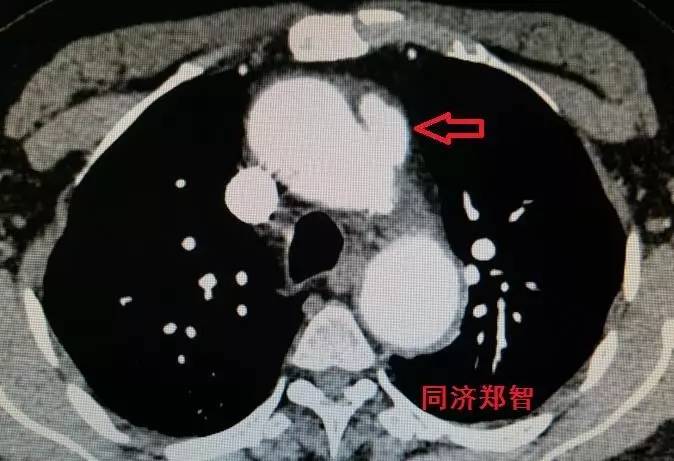

CTA显示升主动脉穿透性溃疡合并壁间血肿(图13)。

图13